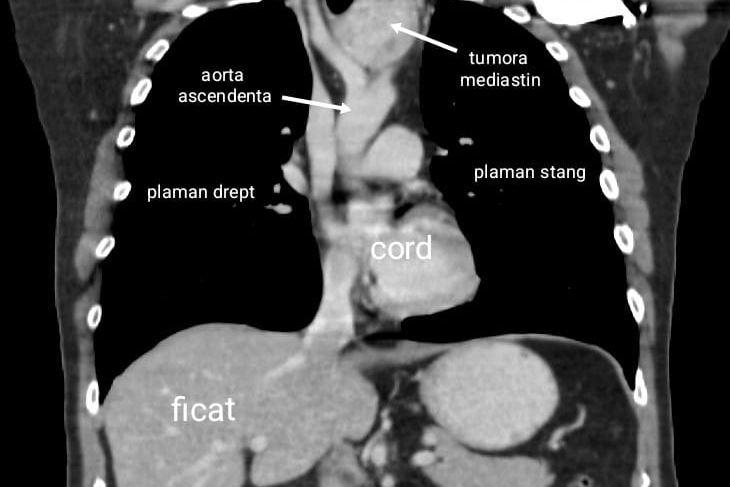

Andrei, aparent sanatos si fara istoric medical semnificativ, a fost infectat cu SARS-CoV-2, iar pentru ca simtea ca nu respira bine si pentru a exclude o posibila pneumonie, s-a orientat catre investigatii imagistice. Examenul CT toracic a evidentiat la nivel mediastinal (zona dintre cei doi plamani) o formatiune tumorala de mari dimensiuni, situata intre arterele mari mediastinale .

Formatiunea voluminoasa de 7 centimetri se intindea de la stern la coloana vertebrala, deplasand spre dreapta traheea si esofagul si era pozitionata intre arterele mari mediastinale, ceea ce facea dificil accesul si extirparea acesteia in conditii de siguranta. Investigatiile au aratat ca tumora era o tiroida ectopica mediastinala nefunctionala, distincta de glanda tiroida normala, ceea ce reprezinta o anomalie extrem de rara, in literatura de specialitate fiind descrise doar cateva cazuri. Din cauza dimensiunilor mari, tiroida ectopica mediastinala trebuia rezecata, cu pastrarea pe loc a tiroidei cervicale normale.